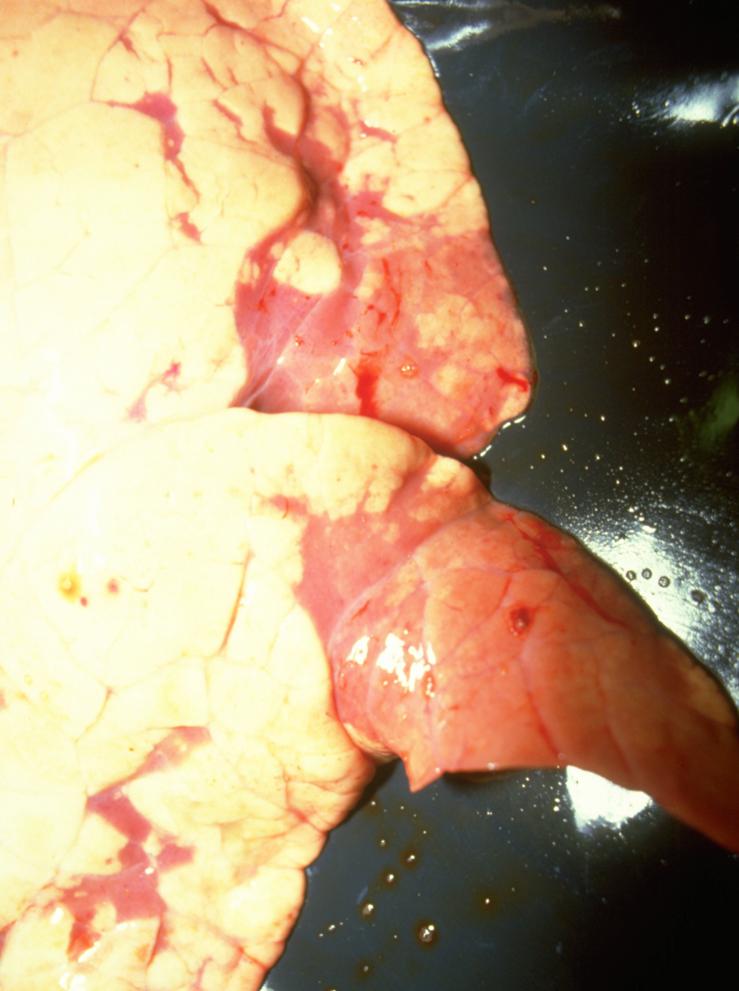

Fig 2: Consolidation typical of SEP

In the herd known to be infected, diagnosis is simply achieved by clinical inspection. A measure of the levels of disease can be obtained by examining batches of pigs at slaughter and measuring the levels of damage in the lungs of 30-50 pigs. The lesions seen are plum coloured, fading to reddish grey as they age, and solid, as shown in fig 2.